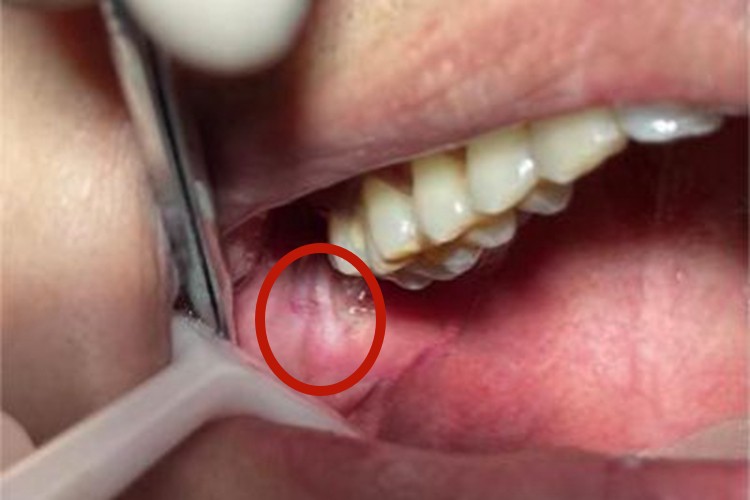

创伤性溃疡口腔黏膜破损后可形成溃疡或糜烂面,开始时可能仅有轻微疼痛或肿胀,溃疡为形态不整,因唾液的浸渍,可使溃疡底发白,周边轻度炎性潮红,自觉疼痛。此外,表面渗出液和唾液混在一起,发生溃疡后可影响进食。

创伤性溃疡主要与口内持久的机械刺激有关,如残冠、残根、不良修复体、锐利的牙齿边缘等。